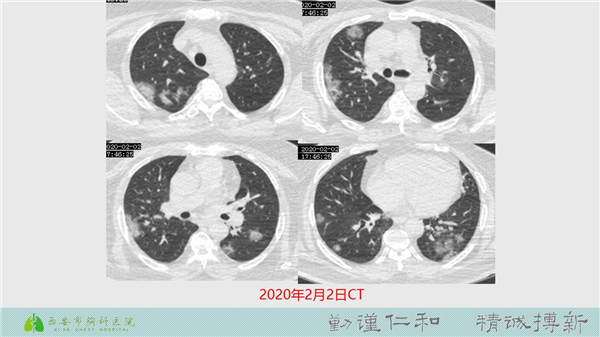

【病例分享】新型冠狀病毒肺炎4例(西安市胸科醫(yī)院)

發(fā)布時(shí)間:2020-02-10  瀏覽量:1793